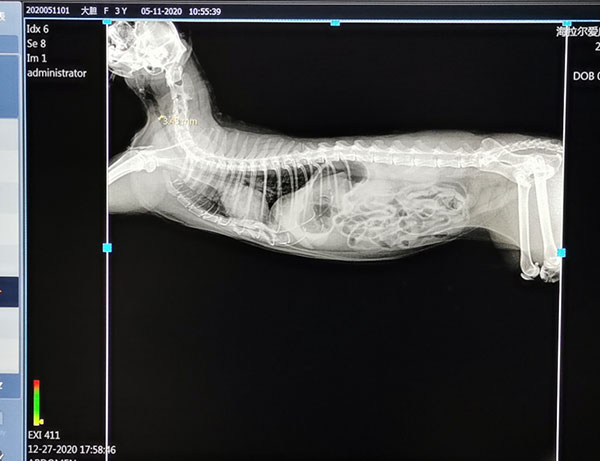

2)影像质量:高质量高稳定的成像质量是购置DR设备的初衷之一,也是提高诊疗水平的物理基础。其涉及放射影像的信噪比、分辩率、清晰度、对比度、细节显示等方面,主要由探测器技术、球管X射线质量、后处理功能、各硬件与计算机操作软件的兼容性决定。